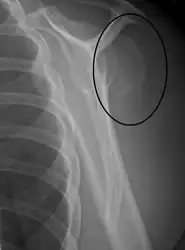

Proximal humerus fracture -

Fracture dislocation of the right shoulder